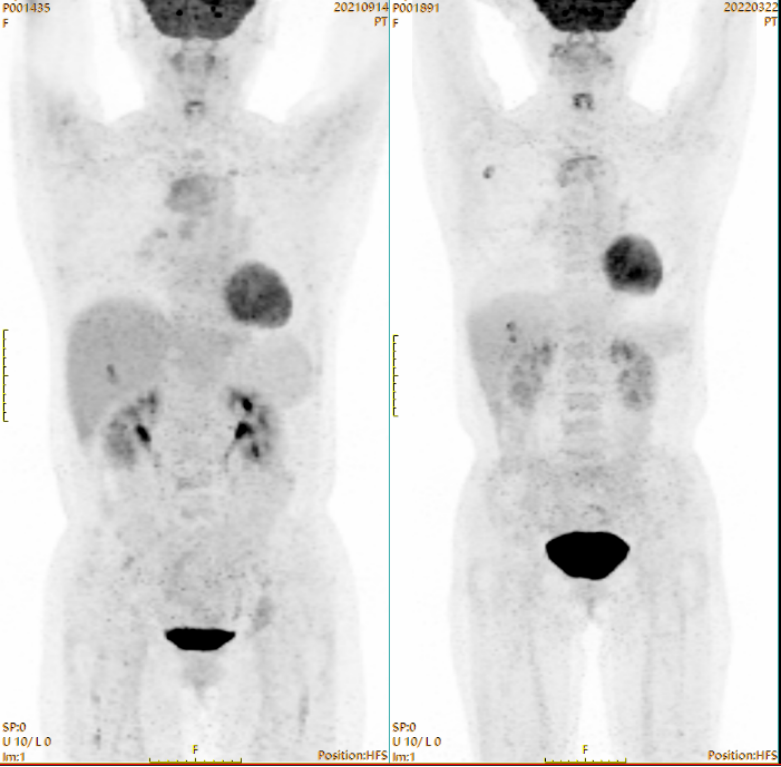

PET-CT检查(6疗程治疗前 vs 治疗后):原胸骨,右前第3肋骨,右侧肩胛骨,T2、4,L4、5椎体,T4、6附件,双侧第11后肋,双侧髂骨,左侧耻骨多发溶骨性骨质破坏伴FDG代谢不同程度增高,SUVmax为6.0;本次骨质破坏灶周边可见硬化边,部分骨质破坏灶内可见高密度影,FDG代谢程度部分较前增高,部分较前减低,SUVmax为7.4;原骨质破坏灶周围FDG代谢增高软组织密度影,本次显像未见明显FDG代谢增高。

640 (3).png

PET-CT检查情况(左:6疗程治疗前,右:6疗程治疗后)